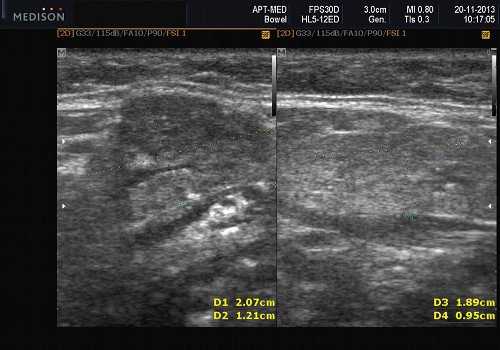

Рис. 3. Сиаладенит правой поднижнечелюстной слюнной железы.

- обструктивные сиаладениты, развивающиеся при затруднении оттока слюны при обструкции выводного протока камнем (рис. 5-7) или сгустившимся секретом, а также вследствие рубцового стеноза протока. По распространенности процесса различают очаговый, диффузный сиаладениты и сиалодохит - воспаление выводного протока. Течение процесса может быть острым и хроническим;

Рис. 5. Камень протока поднижнечелюстной слюнной железы.

Рис. 6. Камень в паренхиме поднижнечелюстной слюнной железы.

Рис. 7. Камень в протоке поднижнечелюстной слюнной железы.